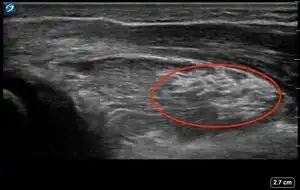

| 4 | Pronator quadratus hematoma[17][14][18] | ![]() Ultrasound view of pronator quadratus hematoma (PQH) sign (area inside red oval) which is identified by an increased thickness and brighter appearance of the pronator quadratus muscle compared to the pronator quadratus muscle of the unaffected forearm. |

Ultrasound Scanning for Pronator Quadratus Hematoma Sign

While the patient has their affected forearm supinated at least 90 degrees, maintain the probe perpendicular to the skin, align the probe with the metaphysis of the distal radius, and increase the depth to 4 cm.

Record a 4 second video while slowly sweeping across the volar (palmar) aspect of the distal forearm until the metaphysis of the distal ulna is in the field of view.

Review the video to obtain an image of the largest section of the pronator quadratus muscle, which is typically the mid-portion of the sweep.

Repeat steps 1-3 with the unaffected forearm for comparison. Compare the thickness and appearance of the pronator quadratus muscle on both sides.

Note whether the affected forearm has a hematoma of the pronator quadratus muscle.